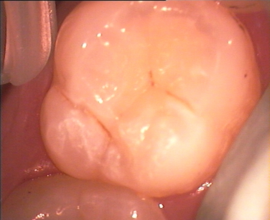

Das selbe Problem haben wir auch bei vermeintlich nur harmlosen Verfärbungen der Zahngruben in den Kauflächen, der sogenannten "Fissuren". Hier ein Beispiel aus unserer Praxis:

Karies, Zahnarzt, Sacha Karmoll Dieser Zahn hat schon eine Karies, zum Glück noch in einem frühen Stadium.

Solche Zähne finden wir häufig bei jugendlichen Patienten vor. Die Schwierigkeit hierbei ist, die richtige Diagnose zu treffen.

Aus meiner Praxiserfahrung mit Neupatienten weiß ich, dass die Vorbehandler, von denen diese Patienten dann zu uns wechselten, solche Zähne entweder gar nicht weiter beachten oder nur insoweit, als dass sie diesen Zahn "weiter beobachten" und/oder "abwarten" wollen.

An dieser Stelle sei dann aber die Frage erlaubt: Was wollen wir denn hier "beobachten" oder "abwarten"? Ich komme gleich wieder auf diese Frage zurück. Schauen wir uns doch erst einmal einen solchen Zahn, so wie er sich auf dem oberen Bild darstellt, im Schliffbild unter einem Mikroskop an: